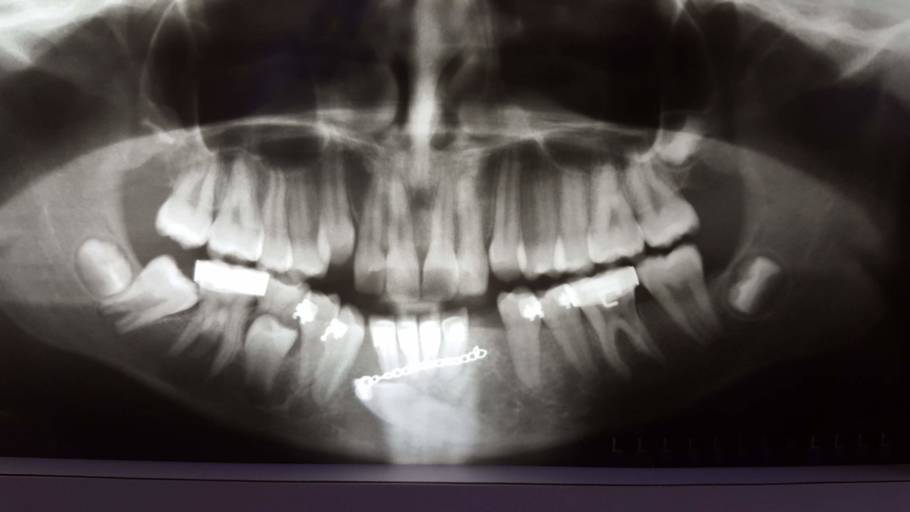

I have a transmigrated mandibular canine. It is very far into my jaw. My orthodontist decided to attach a button onto the tooth, run a chain through my gums and attach it to my 2nd furthest back tooth. This constant pressure is moving the tooth into...

What can this be?

I went for a wisdom tooth removal but they found this space under tooth #24 after doing my X-ray examination.. I’m really scared that I might loose the tooth or have to have a tooth removed. I don’t have any pain with the tooth and no problems as to...